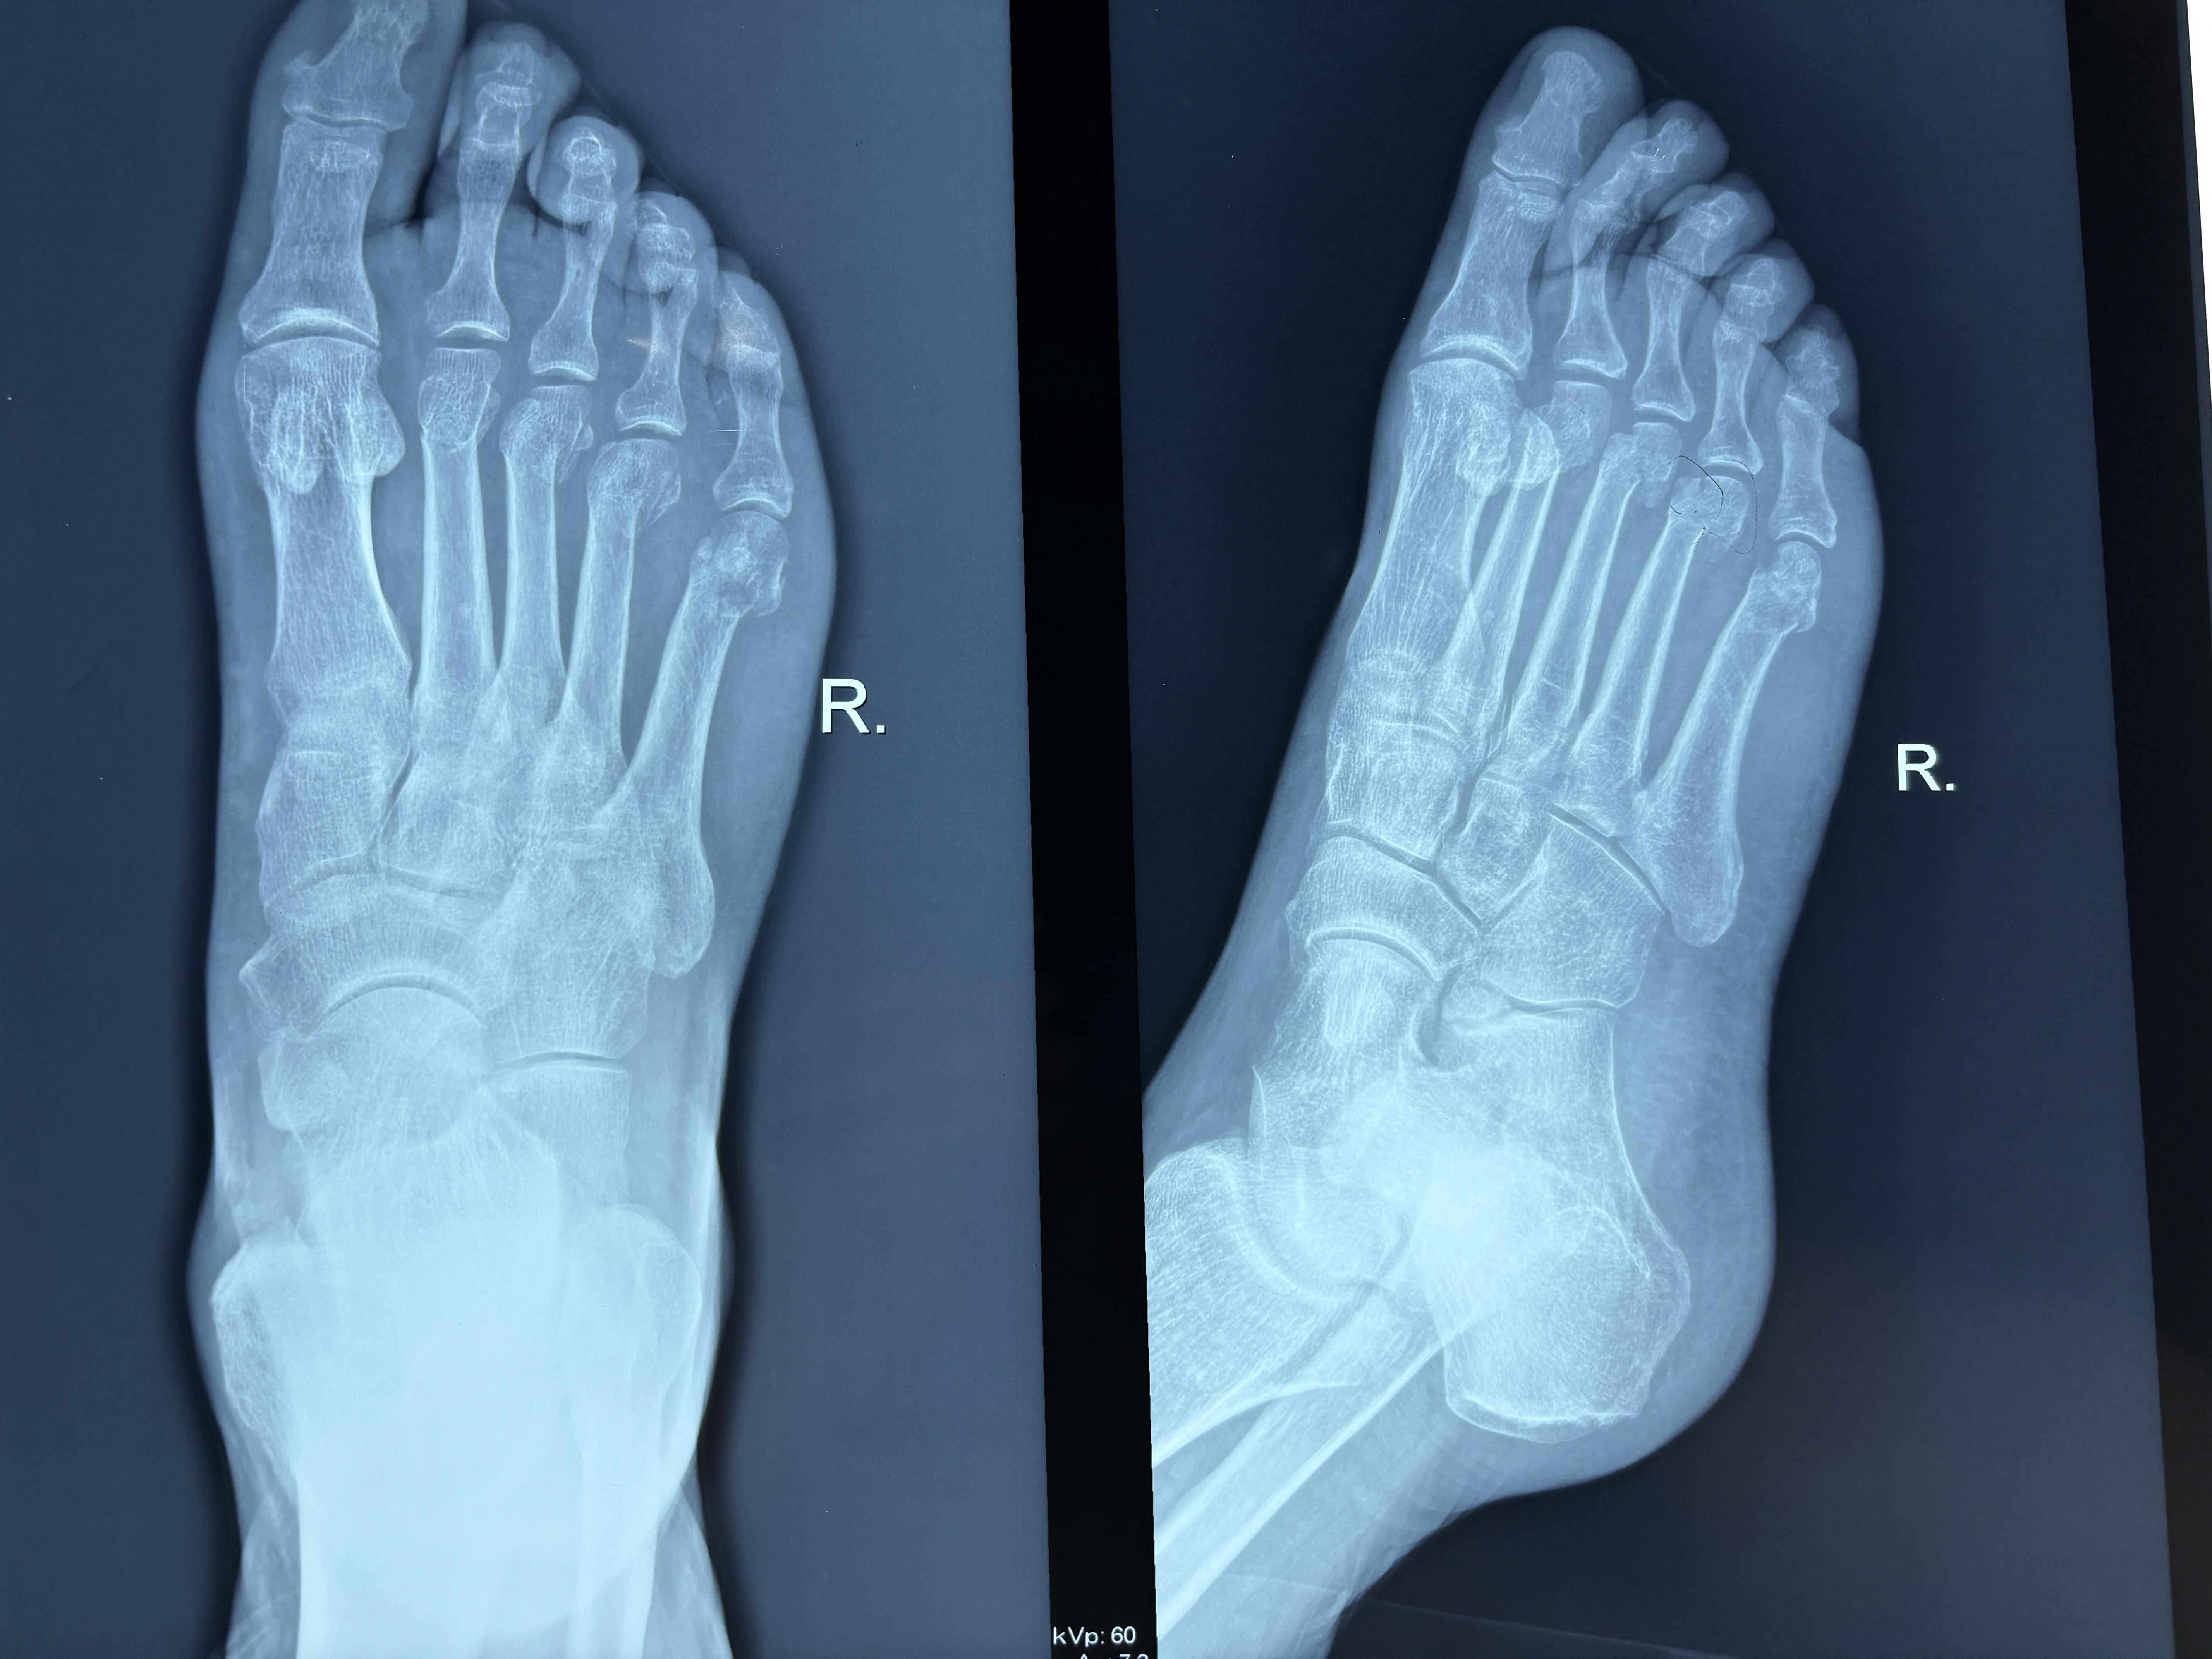

跖骨骨折后一般需6~8周愈合,但具体走路时间因人而异,需综合评估后确定以下是关键要点1 愈合阶段与时间线骨折后1~2周为早期炎症期,断端形成血肿并启动修复3~8周进入原始骨痂形成期,骨折稳定性逐渐增强此后为骨痂塑形期,通过改建恢复骨骼正常形态通常6~8周后骨折初步愈合,但需医生通过。

跖骨骨折后一般8 12周左右逐渐尝试走路,但具体时间因人而异骨折愈合阶段对走路时间的影响初期1 2周骨折后局部肿胀疼痛,需固定处理,不能走路,以稳定骨折部位纤维愈合期3 6周骨折处形成纤维连接,肿胀和疼痛缓解,但不够坚固简单跖骨骨折且骨折端稳定者,可在拐杖辅助。

跖骨骨折后能走路的时间因人而异,通常在3至6个月,但受多种因素影响骨折类型是关键因素之一简单骨折如裂缝骨折因骨连续性破坏小,愈合较快,可能在4至6周初步愈合粉碎性骨折因骨折块多局部血运破坏严重,愈合时间延长,可能需要3至6个月甚至更久患者年龄直接影响愈合速度儿童新陈代谢。